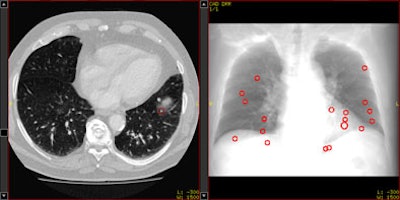

| Above, axial CT image in standard-dose CT (SD-CT) showing a nodule in juxtadiaphragmatic location missed by CAD-1. Above right, CAD markers resulting from the analysis of the SD-CT data presented in a coronal view. Below, CAD analysis of the ultralow-dose CT (ULD-CT) data resulted in automated detection of the corresponding nodule in the left lower lobe. On the right, CAD markers resulting from the analysis of the ULD-CT data. All images courtesy of Dr. Valentina Romano. |

The group compared the results of CAD analysis by assessing detection sensitivity and false-positive detections with ultralow-dose CT (ULD-CT) and standard-dose CT (SD-CT) protocols. Data were collected on 26 patients with known lung cancers.

CT images were consecutively acquired at 5 mAs (ULD-CT) and 75 mAs (SD-CT) with 120 kV tube voltage and 1-mm slice thickness. Images were examined using a soft-tissue kernel as recommended by the manufacturers.

"Ground truth was established by consensus of three experienced radiologists; there were 253 ... nodules ranging from 2 to 41 mm, and each dataset had between one and 28 nodules," Romano said.

The sensitivity results for both systems did not decline significantly for standard-dose protocols versus low-dose settings: for SD-CT and ULD-CT, respectively, the sensitivity for detecting nodules 4 mm and larger was 72% and 73% for the CAD-1 application and 62% and 56% for CAD-2.